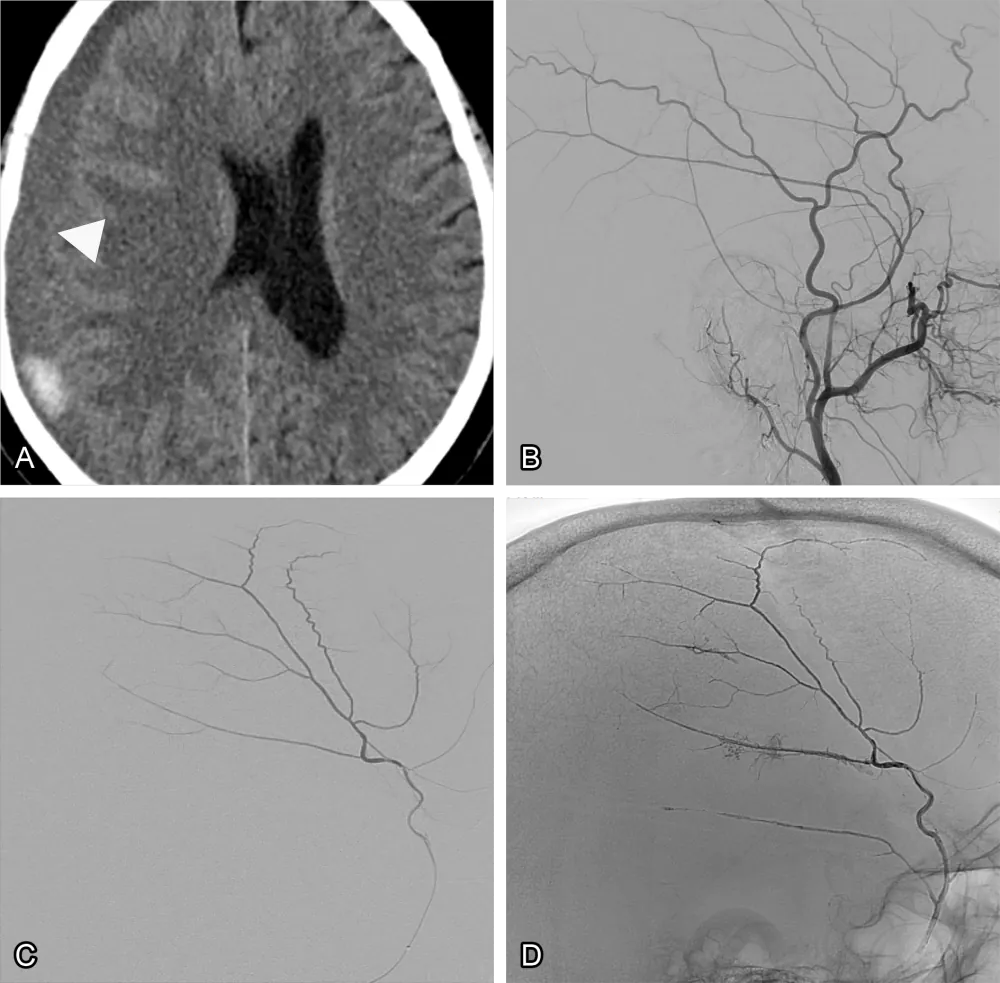

Figure 1: Middle meningeal embolisation of a subdural haematoma. (A) A CT scan of a subdural haematoma (arrowhead). (B) Angiography of the external carotid artery. (C) Selective angiography of the middle meningeal artery. (D) After injection of an embolic agent filling the entire artery.

The procedure is performed by an endovascular specialist. Using X-ray guidance, a thin tube (catheter) is inserted through a small cut in the wrist or groin and carefully threaded through the blood vessels to reach the middle meningeal artery. Once in place, the artery is sealed off using tiny particles, an embolic glue-like substance (fig. 1), or very small coils.

MMA embolisation targets the middle meningeal artery, which supplies blood to the membrane around the haematoma. By blocking this artery, doctors stop the repeated leaks that keep the haematoma alive. Over time, the body can then safely reabsorb the blood.